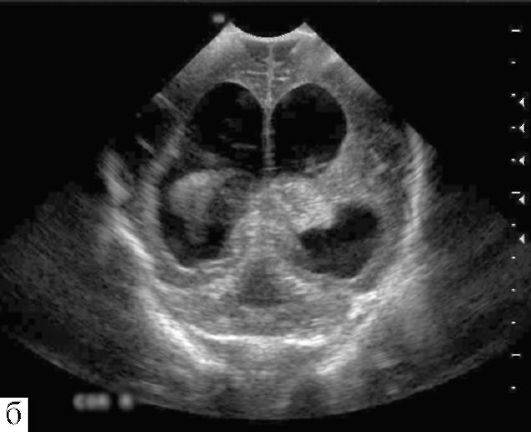

УЗИ проходит благодаря воздействию звуковых волн с настолько высокой частотой, что человеческое ухо не может их воспринимать. При проникновении через организм человека происходит отражение эхо-сигналов с различными скоростными параметрами. Диагностируются процессы, происходящие внутри тела человека.

Часто при обследовании применяется ультразвуковая методика под названием нейросонография, которая с высокой точностью определяет размеры отдельных участков головы, наличие различных аномалий, раковых образований.

При выполнении УЗИ доктор способен узнать структуру исследуемого сосуда, принять решение о функциональной способности, наличии патологических отклонений, дефектах. Метод диагностики носит название: допплерография.

Процедура делится на три вида:

Стандартная форма, которая выглядит, как двухплоскостное обследование – способ дает возможность произвести полноценное исследование, изучив сосуды до места их попадания в каналы, заметив новообразования.

Дуплексная форма – результаты сканирования (отображение сосудистой системы головного мозга) выдаются человеку в образе цветного изображения. Врач имеет детальную картину как внечерепной, так внутричерепной структуры, что кардинально упрощает определение диагноза.

Трехмерное ультразвуковое обследование позволяет создать сопоставимое по информативности с фотографическим отображение сосудов для дальнейшего анализа состояния верификации структурных нарушений. Имеется один минус, который не позволит врачу добиться получения данных о функциональном состоянии кровоснабжения.